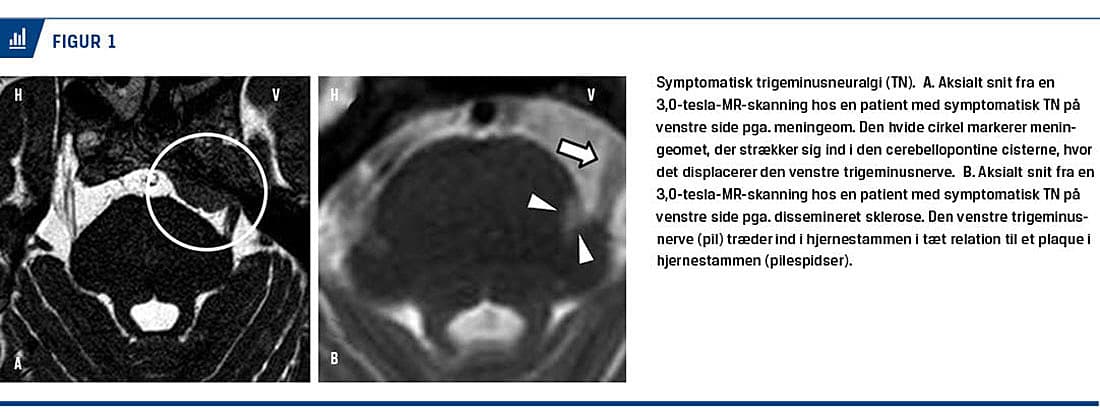

TN inddeles i en klassisk form uden intrakranial patologi og en symptomatisk form, som er sekundær til for eksempel en tumor i den cerebellopontine vinkel eller dissemineret sklerose (Figur 1).

Idet klassisk og symptomatisk TN ikke kan skelnes fra hinanden på baggrund af anamnese og kliniske fund, og eftersom det er vigtigt at vurdere graden af

en eventuel neurovaskulær kontakt, er MR-skanning af cerebrum obligatorisk tidligt i den neurologiske udredning [19]. Der behøver dog ikke foreligge en MR-skanning forud for påbegyndelse af medicinsk behandling, som bør iværksættes med det samme ved smerter, som formodes at være forårsaget af TN.